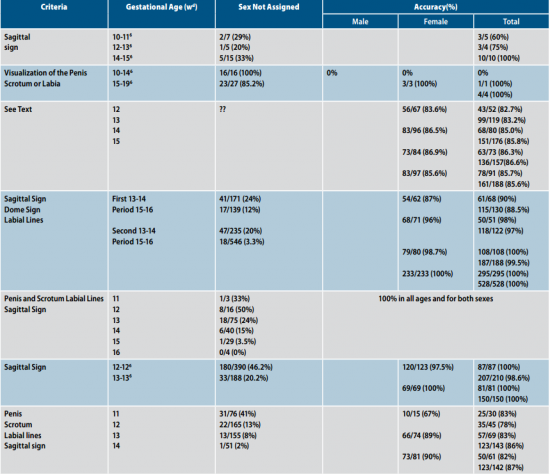

קביעת מין העובר בסוף הטרימסטר הראשון ותחילת הטרימסטר השני

Sagittal sign שתואר לראשונה על ידי Emerson וחבריו[4] הוא הסמן הסונוגרפי המקובל ביותר לקביעת מין העובר בשלבי ההיריון המוקדמים. העובר נסרק בחתכים סגיטליים בקו האמצע. באזור העכוז הנסרק בחתך זה, ניתן לזהות בליטה שמייצגת את הדגדגן או את איבר המין הזכרי. כאשר כיוון הבליטה כלפי מעלה, מין העובר זכר (תמונה 1) וכיוון כלפי מטה מבטא מין נקבה (תמונה 2). שימוש בסמן סונוגרפי זה אפשר לזהות מין העובר ב-71 אחוז (5\7) מהעוברים בשבוע 10 עד 11.9, אך האבחנה הייתה נכונה ב-60 אחוז (3\5) בלבד. דיוק האבחנה עלה עם התקדמות גיל ההיריון ל-75 אחוז, 100 אחוז, 98 אחוז ו-100 אחוז בשבועות 13.9-12, 15.9-14, 16-17.0 ו-18-20.4, בהתאמה[4]. דיווחים רבים אחרים דיווחו על אבחון מין העובר בסוף הטרימסטר הראשון ותחילת השני (14-4) (ראו טבלה 1).

ברונשטיין וחבריו[7] דיווחו שדיוק אבחון מין העובר על ידי אולטרסאונד נרתיקי עולה עם הניסיון, כך שבשנתיים הראשונות לשימוש באולטרסאונד נרתיקי, המין אובחן בדיוק של 76 אחוז ועלה ל-80 אחוז בשנתיים לאחר מכן בין השבועות 13–14 להיריון, ובשבוע 15-16 הדיוק עלה מ-88 אחוז בשנתיים הראשונות לניסיונם ל-96.7 אחוז בשנתיים לאחר מכן. בעבודה זו, מין זכר נקבע על סמך הדגמת מבנה דמוי כיפה (Dome sign) המייצג שק אשכים (תמונה 3) בעוד מין נקבה נקבע על סמך הדגמת שניים או ארבעה קווים מקבילים (Parallel lines) המייצגים את השפתיים הקטנות והגדולות (תמונה 4) . סימנים סונוגרפיים נוספים בעבודה זו[7] היו הדגמת קו אקוגיני הנמשך מבסיס ועד קצה איבר המין הזכרי ומייצג קו האמצע של הפניס (תמונה 5) וכיוון הפאלוס העוברי (כלפי מעלה מייצג זכר וכלפי מטה נקבה).

בניגוד לקביעת המין בטרימסטר הראשון, קביעת המין בטרימסטר השני מבוססת על הדגמה ישירה של איברי המין: שק האשכים והפין אצל זכרים והשפתיים אצל נקבות. טבלה 2 מראה שהדיוק בקביעת מין העובר בטרימסטר השני נע בין 92 אחוז ל-100 אחוז[5][15][16][17][18][19][20][21][22][23]. בחלק מעבודות אלו, הדיוק בקביעת המין היה יותר גדול בנקבות[20][23] ובחלקן בזכרים[5][16]. עבודתו של Natsuyama[6] אינה מופיעה בטבלה 2 מאחר שהוא השתמש בקריטריונים אחרים לקביעת המין כגון מדידת המרחק ה-anogenita והזווית ה-ischiogenita והצליח לאבחן מין העובר ב-99.9 אחוז מהעוברים, אך מדדים אלה לא דווחו בעבודות אחרות.